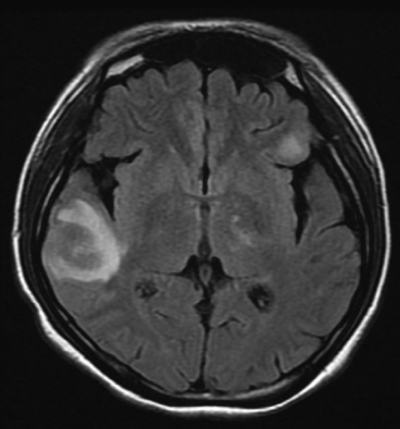

尿所見:蛋白(-)、潜血(-)。血液所見:赤血球 405 万、Hb 11.1 g/dL、Ht 34 %、白血球 2,500(好中球 70 %、好酸球 1 %、好塩基球 1 %、単球 4 %、リンパ球 24 %)、血小板 15 万、PT-INR 1.3(基準 0.9〜1.1)、APTT 38.9 秒(基準対照 32.2)。血液生化学所見:尿素窒素 12 mg/dL、クレアチニン 0.5 mg/dL、Na 140 mEq/L、K 4.0 mEq/L、Cl 108 mEq/L。免疫血清学所見:CRP 0.3 mg/dL、リウマトイド因子<RF>陰性、抗核抗体 1,280 倍(基準 20 以下)、抗 DNA 抗体 60 IU/mL(基準 7以下)、CH50 U/mL(基準 30〜40)、C3 32 mg/dL(基準 52〜112)、C4 3 mg/dL(基準 16〜51)。本日から頭痛、めまい及び嘔吐が出現し、7% 重炭酸ナトリウムを静脈投与されたが改善しない。意識は清明。水平眼振を認める。頭部 CTと頭部 MRI の FLAIR 像とを別に示す。脳脊髄液所見に異常を認めない。